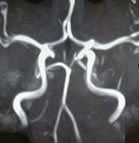

『MR(磁気共鳴装置)にて撮影した画像』

【脳血管】